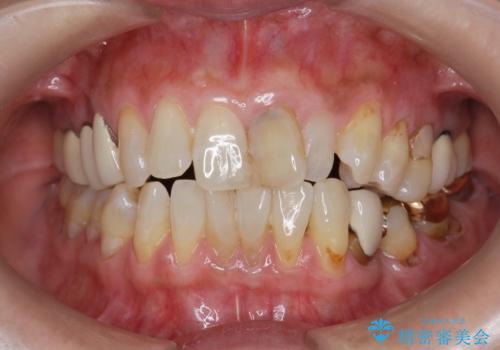

前歯の変色 セラミッククラウンによる審美回復

- 前歯の変色による審美障害の改善を希望され来院されました。

ジルコニアクラウンによる審美性の改善を計画します。

神経の治療をした歯は時間の経過と共に色調の変化が見られます。

このような際、ジルコニアクラウンを装着することで審美性の改善を達成することができます。